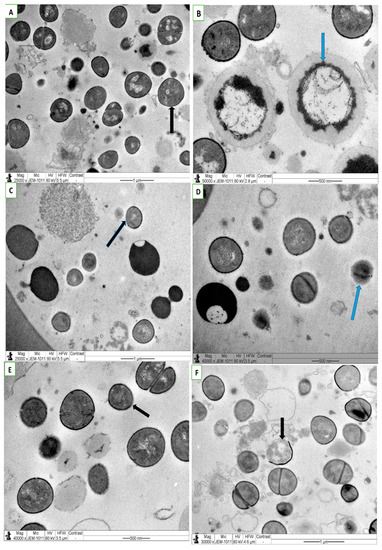

3.4. SEM and TEM Assay on Effect of Combined NS, Antibiotic Treatment